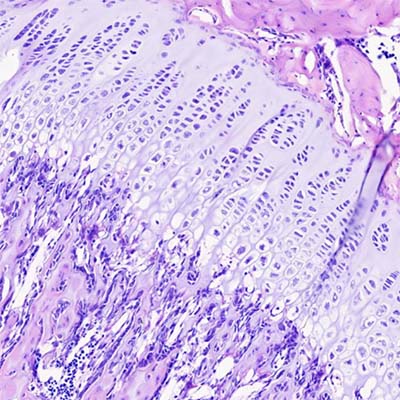

En este entorno vascularizado, el cartílago calcificado sufre una degradación parcial, pero no desaparece por completo de inmediato. Persisten fragmentos en forma de espículas irregulares que actúan como un armazón temporal. Las células osteoprogenitoras se adhieren a estas superficies y se diferencian en osteoblastos, los cuales comienzan a sintetizar osteoide. Este material orgánico se deposita sobre las espículas de cartílago calcificado, generando estructuras híbridas denominadas espículas mixtas, compuestas por un núcleo de cartílago calcificado acelular y una capa superficial de tejido óseo en formación que contiene osteocitos.

Estas espículas mixtas representan una fase transitoria. Con el tiempo, el componente cartilaginoso es completamente reabsorbido, mientras que el tejido óseo continúa creciendo por aposición, aumentando su grosor y resistencia. Algunas de estas estructuras pueden ser remodeladas o incluso eliminadas, mientras que otras se consolidan y contribuyen a la arquitectura definitiva del hueso.